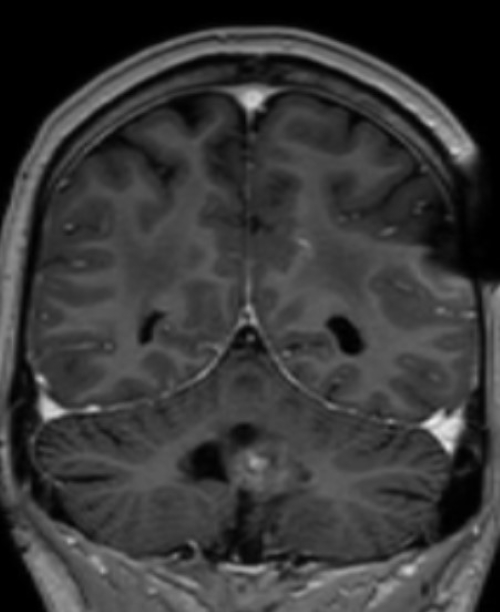

MRT Kopf – was sieht man?

Eine Kopf MRT liefert Ärzte und Radiologen detaillierte Bilder. Zu sehen sind das Gehirn, Schädelknochen, Blutgefäße und anderer umgebende Gewebe im Kopfbereich.

- Tumore und Zysten: Die MRT Kopf kann sowohl gutartige als auch bösartige Tumore im Gehirn erkennen. Sie kann auch bei der Identifizierung von Zysten und anderen strukturellen Anomalien helfen.

- Schlaganfälle und Blutungen: Auf den MRT-Bildern vom Kopf sind frische Schlaganfälle, Hirnblutungen und andere vaskuläre Probleme im Gehirn zu erkennen.

- Entzündungen und Infektionen: Entzündliche Zustände im Gehirn, wie Enzephalitis oder Abszesse, können durch die MRT Kopf Untersuchung identifiziert werden.

- Degenerative Erkrankungen: Die Kopf MRT kann bei der Diagnose degenerativer Erkrankungen wie Alzheimer oder Multipler Sklerose (Link) helfen, indem sie Veränderungen im Gehirngewebe zeigt.